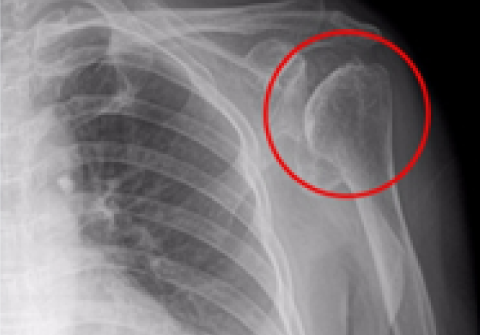

노화된 어깨의 관절낭을 절제해 간격을 넓혀주는 수술방법

어깨 인공관절 역 전치환술

2013.10.05

2013.12.19